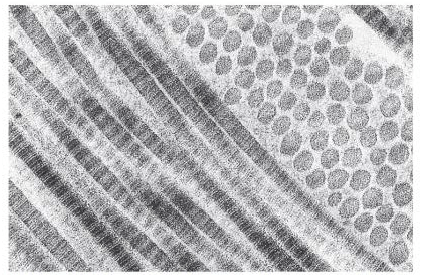

TIPOS DE FIBRAS

Colágena: formadas por subunidades de tropocolágeno. Resisten presión y tensión. Las ubicamos en las cápsulas de las vísceras principalmente.

Reticulares: formadas por Colágena III, forman una red en los órganos y les dan soporte/estructura. Ubicadas en órganos linfoides y endocrinos. Bazo, Hígado, Ganglios linfáticos, riñón.

Elásticas: soportan distensión, ubicadas sobre todo en la pared de la aorta y el ligamento amarillo.